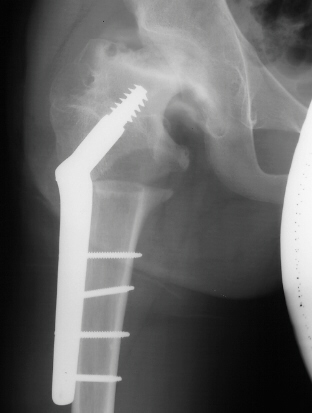

- 2 month Office Follow Up: Rt hip Xray: progressive destruction of capital

femoral epiphysis, cystic changes in metaphysis consistent with AVN.

- Age 6: Valgus osteotomy for subluxation and 2cm leg length inequality.

- Age 15: Valgus osteotomy for hip incongruity.

- Age 20: Hip arthroscopy. Hip fusion recommended.